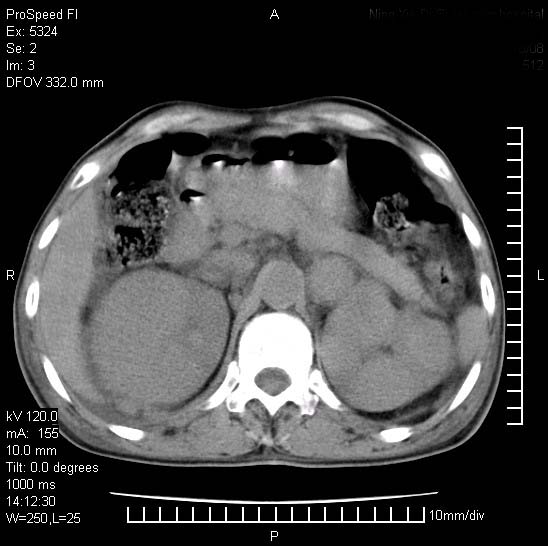

患者阴囊肿大14月,腰痛2个月,咳嗽,咳痰1周,患者现在肾功异常,做增强有些担心,我们用的是欧乃派克.

右侧肾癌伴腹膜后淋巴结转移!

右侧肾癌后腹膜转移,腹腔少量积液

腹膜后淋巴结肿大包饶腔静脉,双肾病变,建议增强

双肾均有软组织密度舯物,腹膜后淋巴结肿大包饶腔静脉------考虑为恶性占位病变,转移瘤可能。

支持:双肾均见软组织密度肿块影,腹膜后淋巴结肿大包绕腔静脉------考虑为恶性占位病变,转移瘤可能。

1)考虑双肾恶性肿瘤(肾癌?)。2)腹膜后淋巴结肿大,多为肿瘤转移所致。

腹腔积液,双肾均有稍高密度肿块,主动脉旁广泛淋巴结肿大,融合,无显著肿块坏死征像,多考虑淋巴瘤累及双肾,不排除肾癌伴转移(肾癌这么大应该较多坏死了),另阴囊肿大,不知是实质肿大还是阴囊积液,如是是积液,多为腹腔肿块压近睾丸静脉所致,如是是实性的,多为淋巴瘤

1、淋巴瘤,双肾转移瘤;2、双侧肾癌,伴有腹膜后淋巴结转移。

双肾均有软组织肿块伴腹膜后淋巴结肿大融合,右侧结肠旁沟积液;考虑恶性肿瘤。转移瘤?淋巴瘤?

双肾增大,腹膜后多发肿大淋巴结影.首先考虑淋巴瘤.

双肾增大,结合腹膜后淋巴结肿大,考虑双肾恶性肿瘤并转移可能。

双肾癌并腹膜后淋巴结转移

考虑恶性淋巴瘤侵及双肾,腹膜后淋巴结肿大。